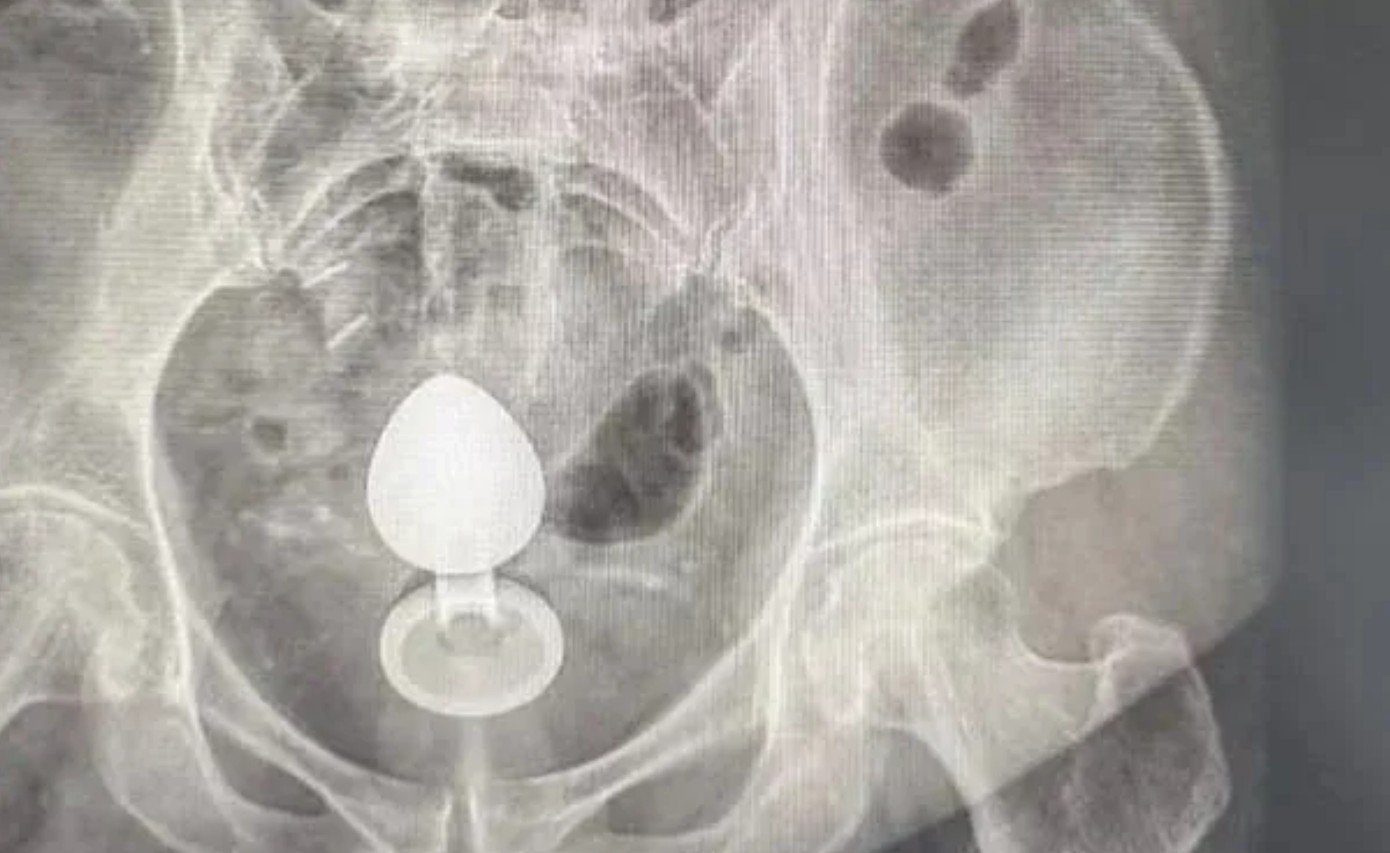

Barbaridade – Um caso inusitado atendido por médicos em uma unidade de saúde serviu como alerta sobre os riscos do uso inadequado de acessórios íntimos. Uma mulher deu entrada no hospital depois que um plug anal ficou preso em seu intestino. Segundo relato ao cirurgião coloproctologista Daniel Brosco, a paciente utilizou o objeto na tentativa de aliviar um quadro de constipação intestinal. No entanto, o acessório “subiu” pelo canal anal e não pôde ser removido por ela mesma.

O incidente ocorreu por volta das 7h da manhã. Cerca de duas horas depois, ao se sentar, a mulher percebeu que o plug havia se deslocado para o interior do corpo. Diante da impossibilidade de retirá-lo, buscou atendimento médico.

De acordo com o especialista, esse tipo de situação pode ser favorecido por dois mecanismos: os movimentos naturais do intestino, chamados de peristaltismo – contrações involuntárias que empurram o conteúdo do órgão – e a formação de um “efeito vácuo” na região retal, que acaba sugando o objeto para dentro.

O médico ressaltou ainda que a paciente apresentava pólipos intestinais, uma condição que torna a parede do intestino mais sensível e aumenta consideravelmente o risco de complicações graves, como perfurações.

Apesar do susto, o plug foi retirado com sucesso e a paciente passa bem. O caso, no entanto, acende um alerta importante: o uso inadequado desse tipo de acessório pode causar lacerações, sangramentos e até perfuração intestinal.